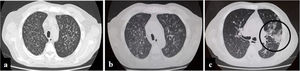

A 57-year-old man, living in San Miguel County, Buenos Aires Province, who had a kidney transplant with cadaveric donor in 2014, was admitted to the emergency department on April 24, 2020, with odynophagia and a history of cough and expectoration for 15 days (Fig. 1). He had been receiving immunosuppressive maintenance therapy including everolimus, mycophenolate mofetil, and meprednisone. The chest computed tomography (CT) image showed diffusely distributed multiple bilateral centrilobular opacities, and a tree-in-bud pattern in both lobes (Fig. 2a).

Evolution of chest computed tomography images. Multiple bilateral centrilobular opacities, with tree-in-bud pattern during first hospitalization. Slight increase of multiple bilateral centrilobular opacities during second hospitalization. Follow-up CT image obtained 10 days later of the third hospitalization shows multifocal peripheral abnormalities (circle) with ground glass pattern involve right lung.

During his hospital stay, on June 16, due to a worsening of the symptoms, and chest CT findings (Fig. 2c), a new nasopharyngeal swab sample for SARS-CoV-2 detection was performed in the context of the COVID-19 pandemic, and viral RNA was detected.

Finally, COVID-19 was suspected because, when the patient had already been diagnosed with histoplasmosis, on day 10 of the antifungal therapy, his respiratory symptoms had worsened. A new CT showed progression of abnormalities with unifocal and peripheral lesions in the right lung with a characteristic ground glass pattern compatible with coronavirus disease5.